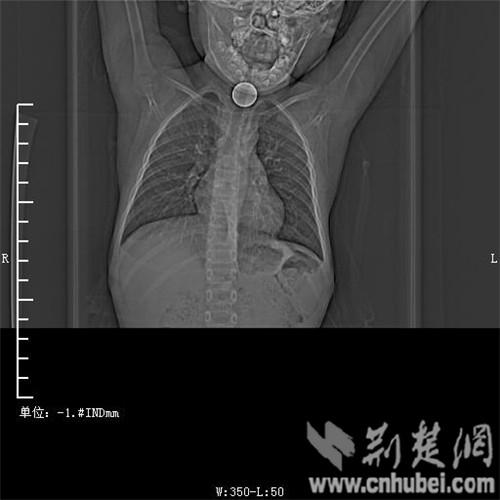

圖為:硬幣卡在了陽陽的喉部

消化內主任方向明告訴記者,孩子送來時已經是晚上8點15分,醫護人員立即給孩子拍胸部CT確定硬幣的位置,8點30分,方向明通過胃鏡下食管異物取出術,成功的將這枚一元硬幣取了出來。1月5日上午,陽陽順利出院,醫生護士在他出院時不斷告訴他,以后千萬不要吞含異物。